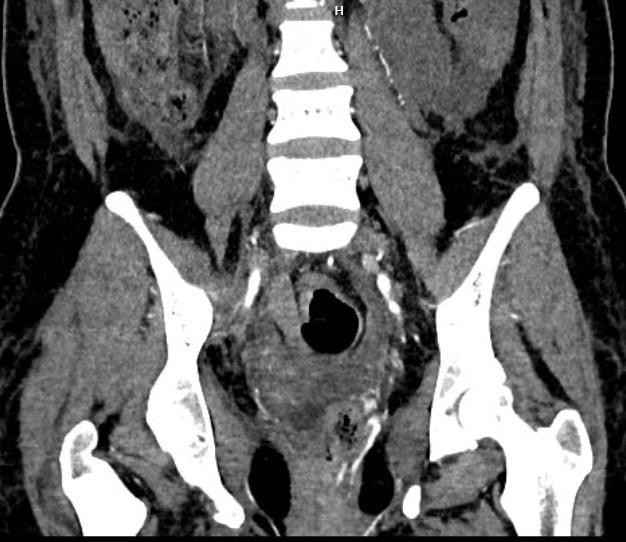

Tại Bệnh viện Bạch Mai, các bác sĩ của Trung tâm Cấp cứu A9 và Trung tâm Điện quang lập tức hội chẩn cấp cứu để đưa ra phương án chẩn đoán và điều trị cho người bệnh. Kết quả chụp cắt lớp điện toán đa lớp cắt (MSCT) cho thấy bệnh nhân bị tổn thương chảy máu từ mạch máu quanh trực tràng.

Với bệnh nhân này, các bác sĩ đã tìm thêm các nhánh chảy máu quanh trực tràng, gồm 6 nhánh mạch 2 bên: động mạch trực tràng trên, động mạch trực tràng giữa và động mạch trực tràng dưới. Sau khi xác định được nhánh chảy máu, các bác sĩ đã lựa chọn vật liệu gây tắc mạch cũng như vị trí can thiệp để không bị hoại tử trực tràng. Sau 36 tiếng theo dõi, sản phụ đã được xuất viện, trở về nhà cùng chồng và 3 con nhỏ.